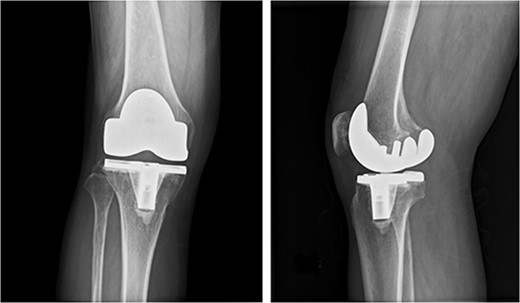

One week earlier, he had visited a local doctor with pain and swelling in his right knee. Cloudy synovial fluid was aspirated from the right knee and PJI was suspected. He was referred to our hospital on the same day and presented with pain, swelling, warmth and redness in the right knee and a slight fever. A plain radiograph showed no aseptic loosening (Fig. 1). An alpha defensin test (Synovasure, Zimmer-Biomet, Warsaw, IN) on synovial fluid was positive [6], and PJI was diagnosed. He was admitted on the same day and scheduled for surgical knee debridement on the following day.

Preoperative anteroposterior and lateral radiographs of the knee show no evidence of aseptic loosening.